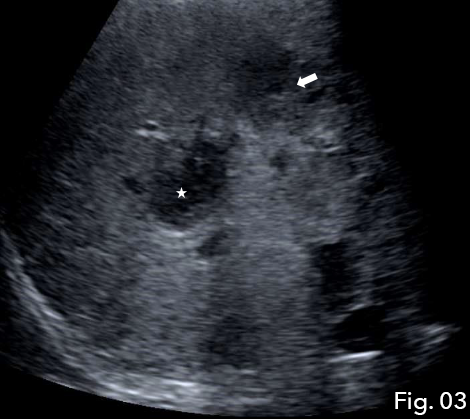

When there was minimal drainage from the catheter, a repeat ultrasound was undertaken to assess resolution. B-mode ultrasound demonstrated a solid low reflective area, presumed to be an abscess with a drainage catheter correctly positioned (Fig 2). The abscess had reduced in size in comparison with the previous examination, however, a new hypoechoic region was noted superiorly to the first abscess (Fig 3) giving rise to suspicion of new abscess formation. IV and IC CEUS were undertaken following local protocols. IV CEUS utilised 2.4 ml of SonoVue (Bracco, Milan) administered through a cannula situated in the left antecubital fossa, followed by a 10ml bolus of saline solution. IC CEUS utilised 0.1 ml of SonoVue (Bracco, Milan) diluted in 50 ml of saline administered via the hepatic drainage catheter.

Fig 3: The abscess had reduced in size in comparison with the previous examination (star), however, new hypoechoic region was noted superiorly to the first abscess (arrow).